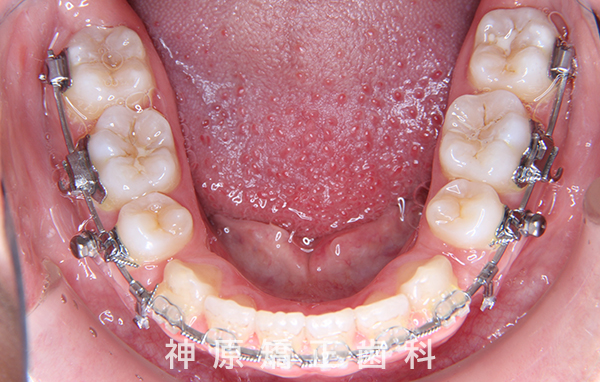

下顎:唇側矯正装置

歯科矯正用アンカースクリュー - 抜歯 / 非抜歯

マルチブラケット装着1年後

口元の突出感を改善するために小臼歯の抜歯が必要と判断しました。抜歯スペースを活用し、前歯を可能な限り後方へ移動させるため、上下に矯正用アンカースクリューを使用する計画です。患者様とご家族に十分な説明を行い、治療ゴールに同意を得た上で矯正治療を開始しました。矯正治療の結果、側貌はE-lineに調和したバランスの良い仕上がりとなりました。